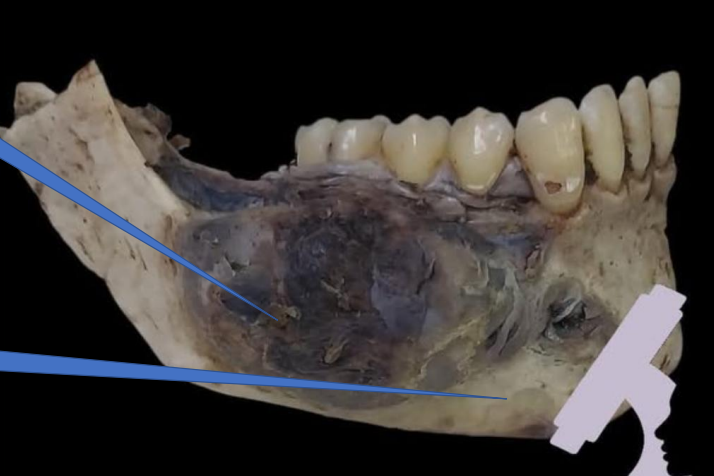

1- Mandible

1- Tumor

2- Mandible